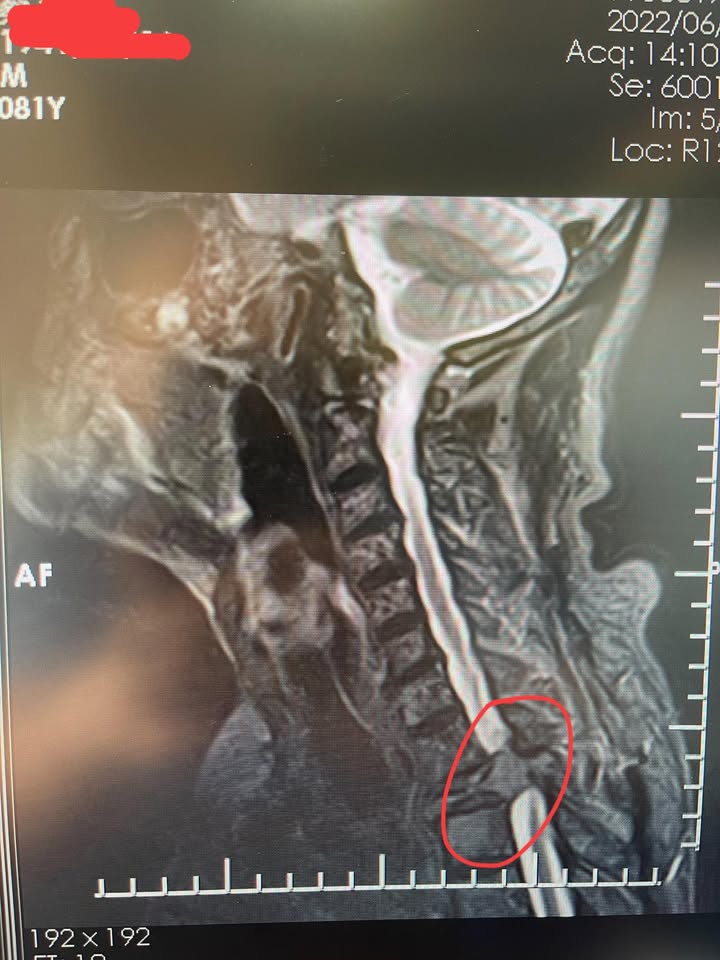

Cervical Spine Treatment Cases 頸椎治療案例 「特殊案例頸椎壓迫三個神外說可能開刀」 「我不是怕開刀,我是怕一輩子變成鋼鐵人…... 2025.07.17 頸椎問題,不只是痠痛,合併多年慢性長期頭痛,還有胸悶心悸,完全找不出原因 「頸椎病症候群」長期困擾?20年頸椎酸痛案例分享,如何快速改善膏肓疼痛 2018.11.10 交感神經型頸椎病導致呼吸困難?49歲患者兩月逆轉重生的中醫微創案例分享 2023.04.18 C4~C7神經根型頸椎病導致手麻痠痛!12次療程實例見證非手術解方 2023.01.30 頸椎鈣化引起脊髓壓迫?中醫解密OPLL後縱韌帶骨化,預防與治療一次搞懂 2023.01.13 神經根型頸椎病合併筋膜發炎?中醫微創療程13次改善五年疼痛困擾 2022.12.28 耳鳴、眩暈、手麻不斷?50歲患者頸椎病纏身4年,中醫14次療程明顯改善 2022.12.03 一分鐘了解神經根型頸椎病:肩頸痠痛不是小事!10次治療症狀幾乎消失 2022.11.11 MRI實拍見證頸椎改善!他擺脫止痛藥依賴,中醫療法讓椎管空間變大了 2022.10.05 耳鳴不是耳朵的錯?頸椎壓迫導致腦鳴、失眠,中醫14次療程讓症狀全消 2022.09.22 手麻原因不只滑手機!醫師解析最常見三大問題+頸椎病11年真實案例 2022.09.29 頸椎重度壓迫導致癱瘓?術後血腫+雙腿無力,中醫針療竟助恢復站立與握力 2022.08.27 頸椎過直不是小事!頭痛手麻痠痛一籮筐|中醫師告訴你正確坐姿怎麼坐 2022.07.24 你以為是胃的問題,其實是脖子的錯?一文看懂交感神經型頸椎病的5大症狀 2022.07.08 ← 上一頁 1 2 3 4 5 下一頁 →